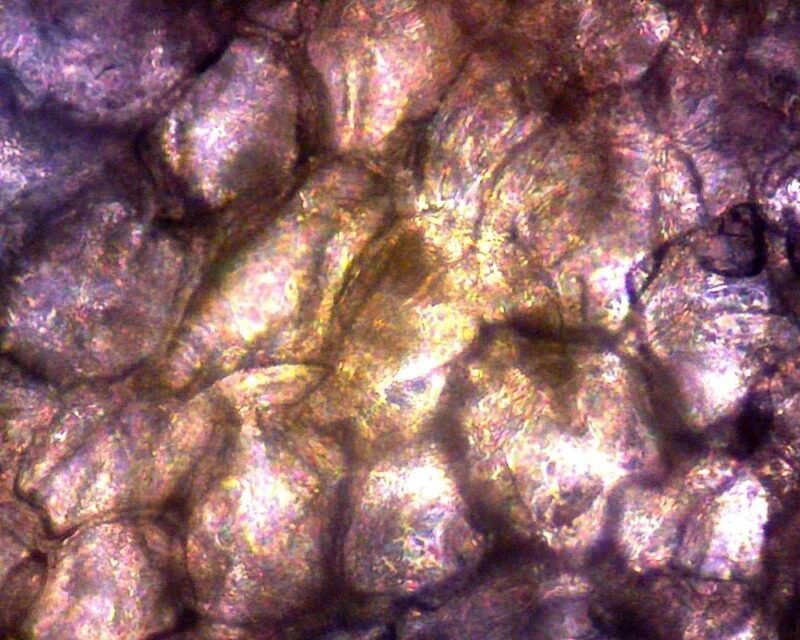

- Veterinary cytology with case record image capture

- Microbiology, parasitology, urinalysis with image archive

Which veterinary cytology / histology slides does this microscope read? Routine veterinary cytology smears (FNA, ear cytology, urine sediment), histopathology slides, fecal flotation / direct smear, urinalysis sediment, and hematology (Diff-Quik / Wright-Giemsa stained) workflow.